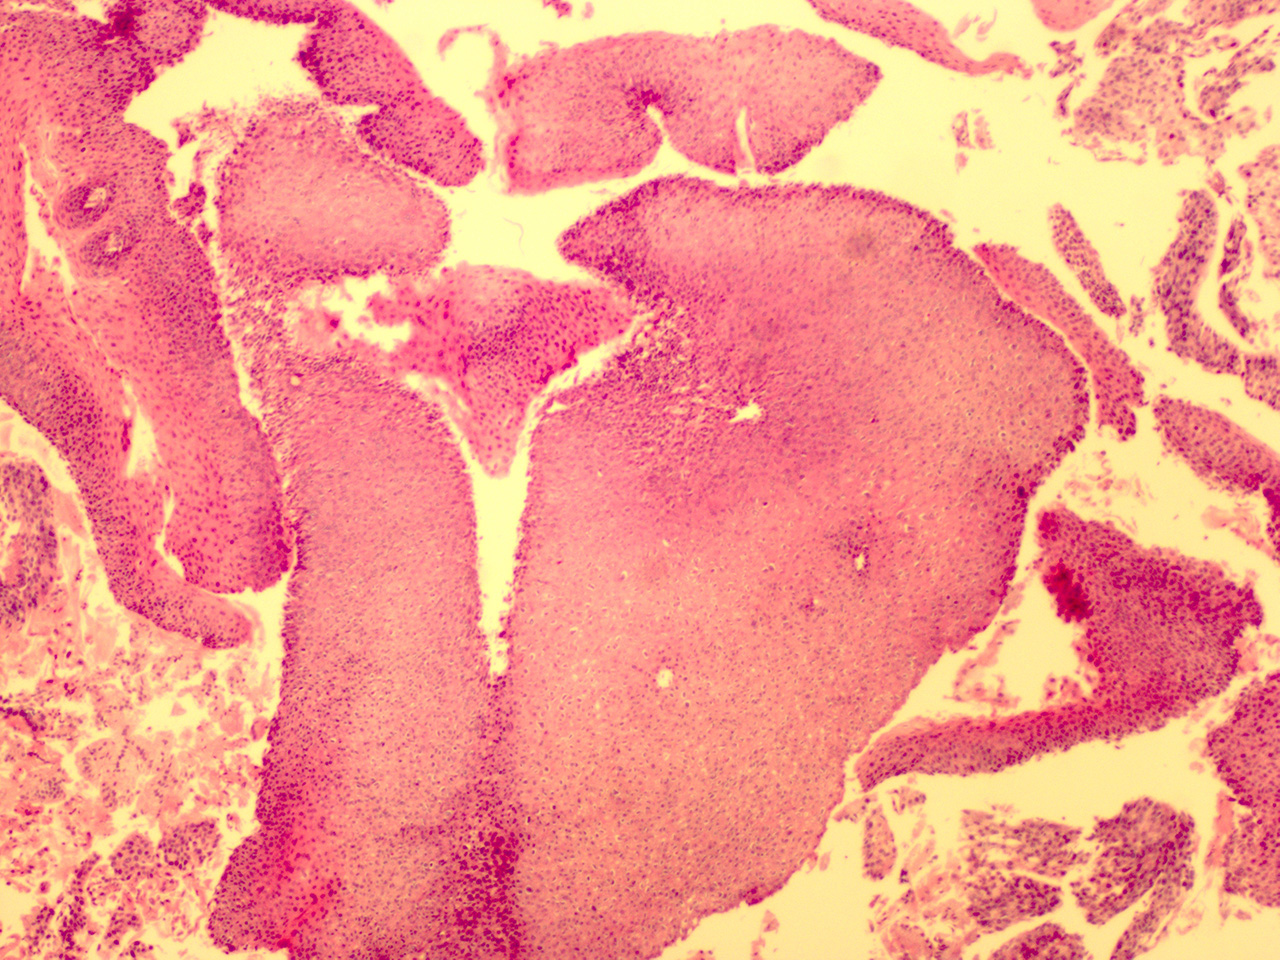

Case 3

Soft Bx CIN 2-3 10x - Low Power